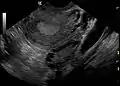

A polycystic ovary

The syndrome acquired its most widely used name due to the common sign on ultrasound examination of multiple (poly) ovarian cysts. These "cysts" are actually immature follicles not cysts. The follicles have developed from primordial follicles, but the development has stopped ("arrested") at an early antral stage due to the disturbed ovarian function. The follicles may be oriented along the ovarian periphery, appearing as a 'string of pearls' on ultrasound examination.

• Gynecologic ultrasonography, specifically looking for small ovarian follicles. These are believed to be the result of disturbed ovarian function with failed ovulation, reflected by the infrequent or absent menstruation that is typical of the condition. In a normal menstrual cycle, one egg is released from a dominant follicle – in essence, a cyst that bursts to release the egg. After ovulation, the follicle remnant is transformed into a progesterone-producing corpus luteum, which shrinks and disappears after approximately 12–14 days. In PCOS, there is a so-called "follicular arrest"; i.e., several follicles develop to a size of 5–7 mm, but not further. No single follicle reaches the preovulatory size (16 mm or more). According to the Rotterdam criteria, which are widely used for diagnosis,[10] 12 or more small follicles should be seen in an ovary on ultrasound examination.[20] More recent research suggests that there should be at least 25 follicles in an ovary to designate it as having polycystic ovarian morphology (PCOM) in women aged 18–35 years.[88] The follicles may be oriented in the periphery, giving the appearance of a 'string of pearls'.[89] If a high resolution transvaginal ultrasonography machine is not available, an ovarian volume of at least 10 ml is regarded as an acceptable definition of having polycystic ovarian morphology instead of follicle count.[88]